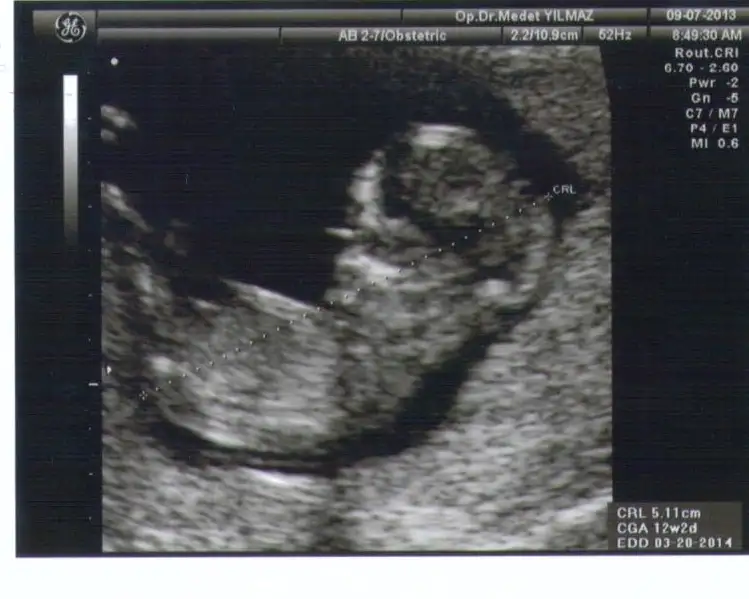

kızlar benim bebeğimiçin de yorum yapar mısınız? bu resimlerde 12+4 haftalık....

gurbet güzeli,orkdm ve diğer anlayan arkadaşlar...cevaplarınızı bekliyorum. $bebişim.webp $bebişim2.webp